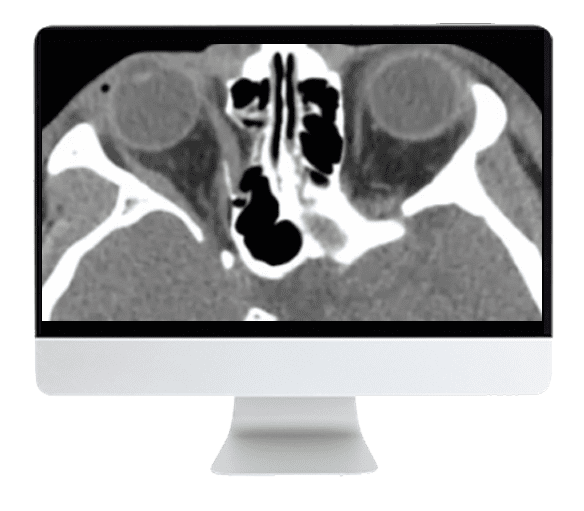

ARRS Imaging Victims of Violence: Fists, Stabs, Bullets, and Blasts 2021 (CME VIDEOS)

Clarifying both the common and uncommon imaging findings associated with fist fights, penetrating trauma, and other explosive injuries to enhance patient care, this Online Course will also address the radiologist’s role in Mass Casualty Activations, which can incorporate any and all of the aforementioned injury mechanisms.